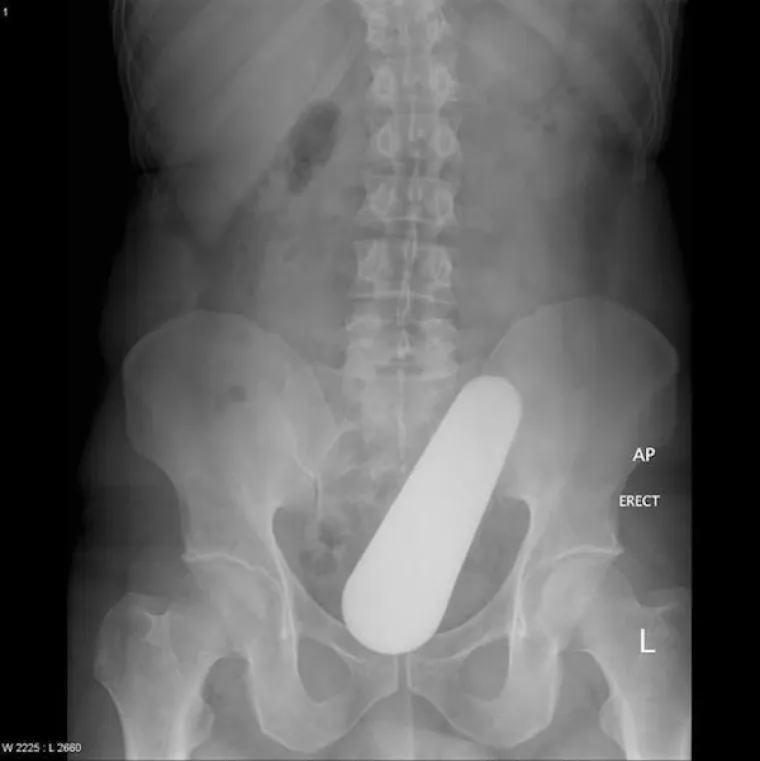

LJUDI SU ČAROBNO SPREMIŠTE, U NJIH STANE BAŠ SVE: Nevjerojatne snimke pokazuju što su sve uspjeli ugurati u sebe